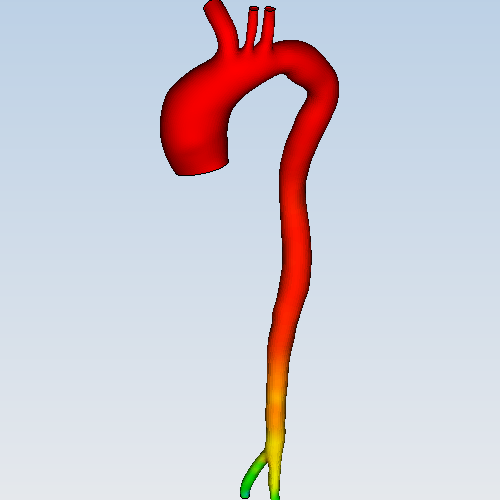

- 8 主动脉血流动力学仿真

流体 | 主动脉血流动力学仿真APP用于描述主动脉里的血流动力学情况。血液在主动脉里流动过程中,会根据血管形态改变流速与压力,沿途会有部分血液进入分支血管。主动脉血流动力学仿...